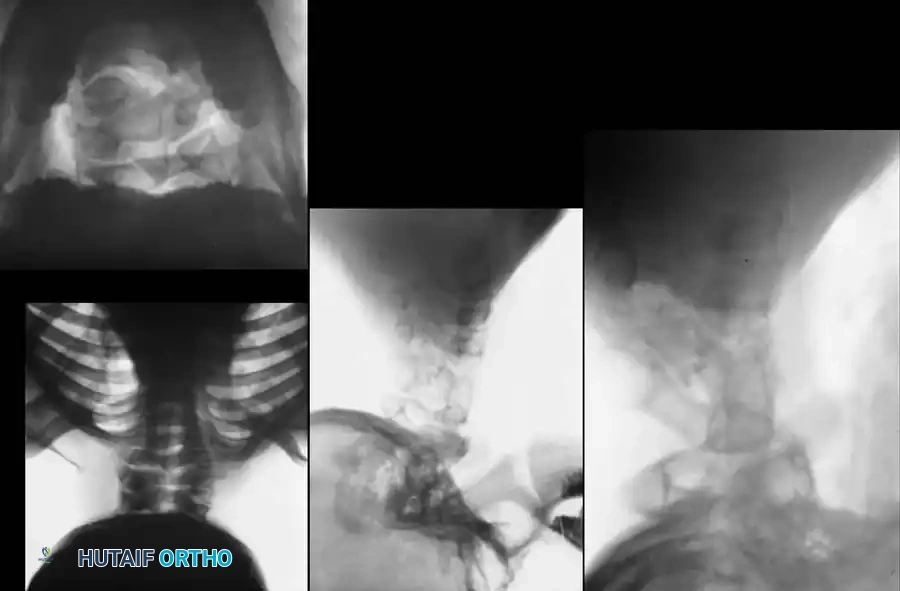

RADIOGRAPHIC EVALUATION

A comprehensive imaging protocol is the cornerstone of KFS management.

Initial evaluation must include high-quality anteroposterior (AP), open-mouth odontoid, and lateral cervical radiographs.

Dynamic Imaging

Lateral flexion-extension views are the most critical plain films obtained. They are essential for identifying occult atlantoaxial instability or hypermobility at an open segment adjacent to a fusion block.

Advanced Imaging (CT and MRI)

- Computed Tomography (CT): 3D CT reconstructions are invaluable for delineating complex bony anatomy, identifying hemivertebrae, and planning surgical screw trajectories in dysplastic pedicles or lateral masses.